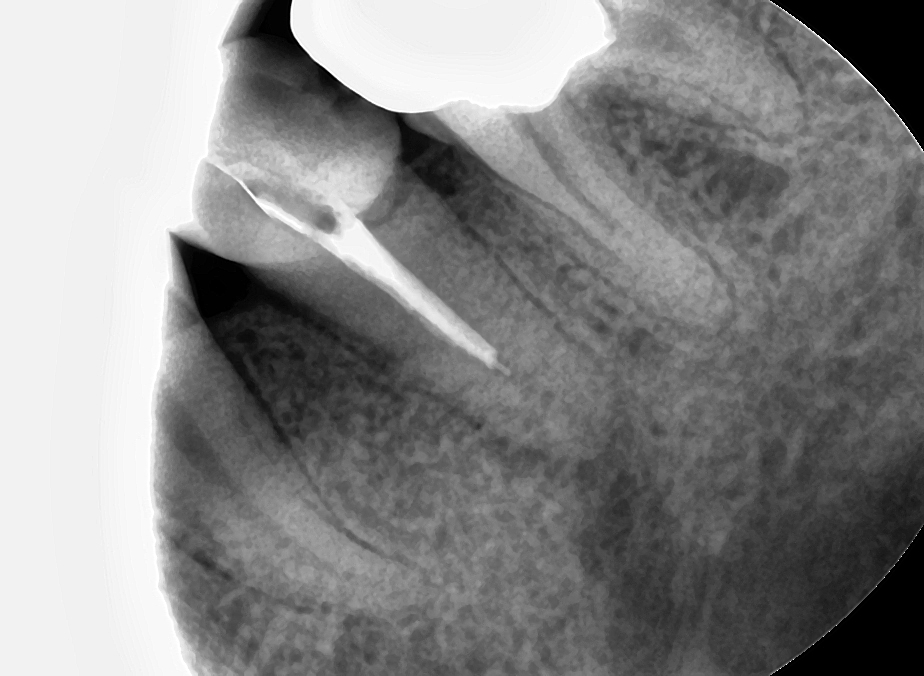

아 근데 잘 한 것만 올리니까 동기들이 오해하는 것 같으니 이번엔 잘 못한 것도 하나 올려봐야겠다. 근관치료하시는 동안 굉장히 아파하셨던 분, 특히 CF하는 날에는 일단 마취를 안하고 진행하는데 굉장히 화들짝 놀라는 듯이 통증을 호소하셔서 마취 후에 필링했던 분이다. 물론 마취를 했는데도 아파하셨지만...

좌) 저번주 첫 필링 당시 사진 / 우) 이번주 다시 필링

보다시피 처참하게 언더필링이 돼서 진짜 깜짝 놀랐다. 아니 왜 저 자리에서 0.5사인이 나는 거지? root ZX만 믿었다가는 이렇게 되는구나. 그러니까 아파하시지🤦♂️ 필링 후에 다른 체어 진료 계속 뛰다가 뒤늦게 필링 사진 열어보고서는 진짜 깜짝 놀랐었다. 그래도 차트에 내가 WLD다시하고 CF도 다시 한다고 적어놨었고 목요일에 마침 오셔서 GP 다 긁어내고 세척 소독 한 다음 이번엔 제대로 워킹랭쓰 재고(근데 이번에도 저 위치에서 또 0.5사인 뜨더라.. 무시하고 더 집어 넣으니까 신호가 죽었다가 다시 살아남;;) 필링 해냈다. 휴~

근데 이거는 root ZX로 잰 워킹랭쓰까지 다 넣었는데 언더난 거고, CF날 임시가봉제 제거하고 GP콘 넣어보면 저번에 잰 워킹랭쓰까지 잘 안들어가는 경우가 많은데, 그런 경우 보통 원장님들께서는 Gp콘 사이즈 오차를 많이 말씀하시지만 초보자에게 더 흔한 오류는 ①WLD할 때 reference point를 일정하게 잡지 않고 이상한데다 잡았거나(straight line access 문제), ②근관의 taper와 GP콘 taper가 서로 안맞거나(이때는 taper 큰 파일로 훑어주거나, 아니면 circumferential filing을 해주면 들어간다)인 경우도 많은 것 같다. 진짜 드물게 임시가봉할 때 넣어놨던 cotton pellet이 MAF확인한다고 핸드파일 집어 넣다가 근관 끝까지 다져넣어 끼일 수도 있다고 한다. 그런 일은 없어야겠지만, 아무튼 워킹랭쓰까지 안들어가면 root ZX를 다시 한 번 써서 확실하게 워킹랭쓰를 다시 잡고 가야하는 게 맞는데.